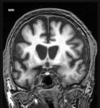

Q

A

Esclerose mesial temporal

Observe a perda de volume, que indica atrofia e causa aumento secundário do corno temporal do ventrículo lateral.

O sinal alto no hipocampo reflete a gliose.

How well did you know this?

Qual o padrão da Esclerose mesial temporal?

Atrofia hipocampal e hipersinal T2. Cerca de 10% dos casos são bilaterais (dificulta o diagnóstico). A etiologia é desconhecida, mas há uma relação entre STM e convulsões febris prolongadas no início da vida A esclerose mesial temporal pode ocorrer em associação com outras patologias, principalmente displasia cortical focal (dual pathology).